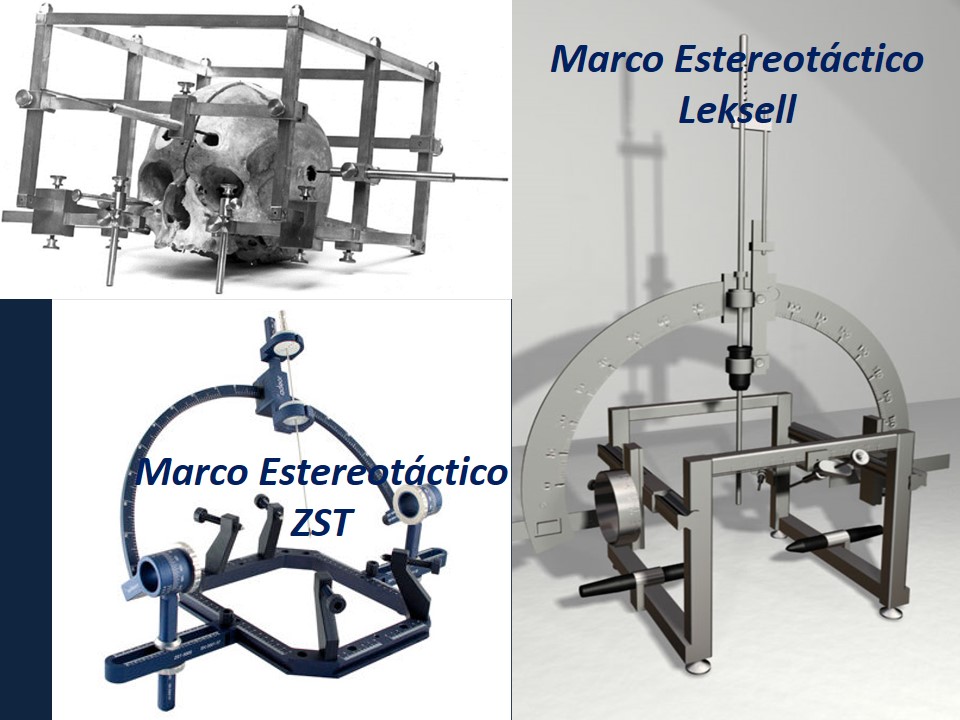

Metodología Estereotáctica o Estereotaxia